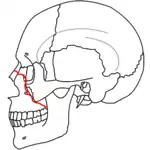

| Le Fort III fractures | |

At the beginning of the 20th century, René Le Fort mapped typical locations for facial fractures; these are now known as Le Fort I, II, and III fractures (right).[7] Le Fort I fractures, also called Guérin or horizontal maxillary fractures,[14] involve the maxilla, separating it from the palate.[15] Le Fort II fractures, also called pyramidal fractures of the maxilla,[16] cross the nasal bones and the orbital rim.[15] Le Fort III fractures, also called craniofacial disjunction and transverse facial fractures,[17] cross the front of the maxilla and involve the lacrimal bone, the lamina papyracea, and the orbital floor, and often involve the ethmoid bone,[15] are the most serious.[18] Le Fort fractures, which account for 10–20% of facial fractures, are often associated with other serious injuries.[15] Le Fort made his classifications based on work with cadaver skulls, and the classification system has been criticized as imprecise and simplistic since most midface fractures involve a combination of Le Fort fractures.[15] Although most facial fractures do not follow the patterns described by Le Fort precisely, the system is still used to categorize injuries.[5]